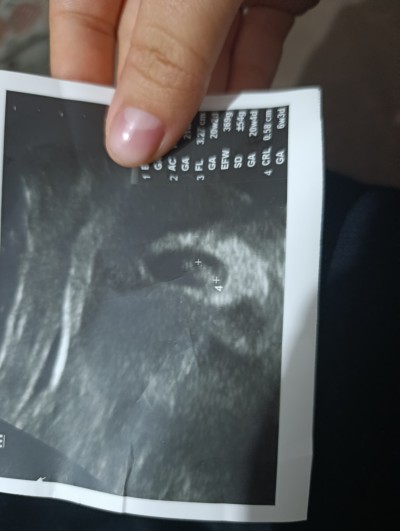

Ben bugün gittim 6 hafta 3 günlük kese oluşmuş dedim yolk sac varmı diye yolk sac değil farklı birşey dedi

image

anlamadm bende

Alttan ultrasonmu yapti benimde aynı böyle cikti ama bebeğe benziyordu kalp atışı oldumu senin

8 Aralık 2025 (34 puan) yorumladı

Yok normal karindan baktı kalp atışıyla ilgili birşey dmedi bir ay sonra gel dedi ben iki hafta sonra başka doktora gidecm begenmdm doktoru ilgisizdi